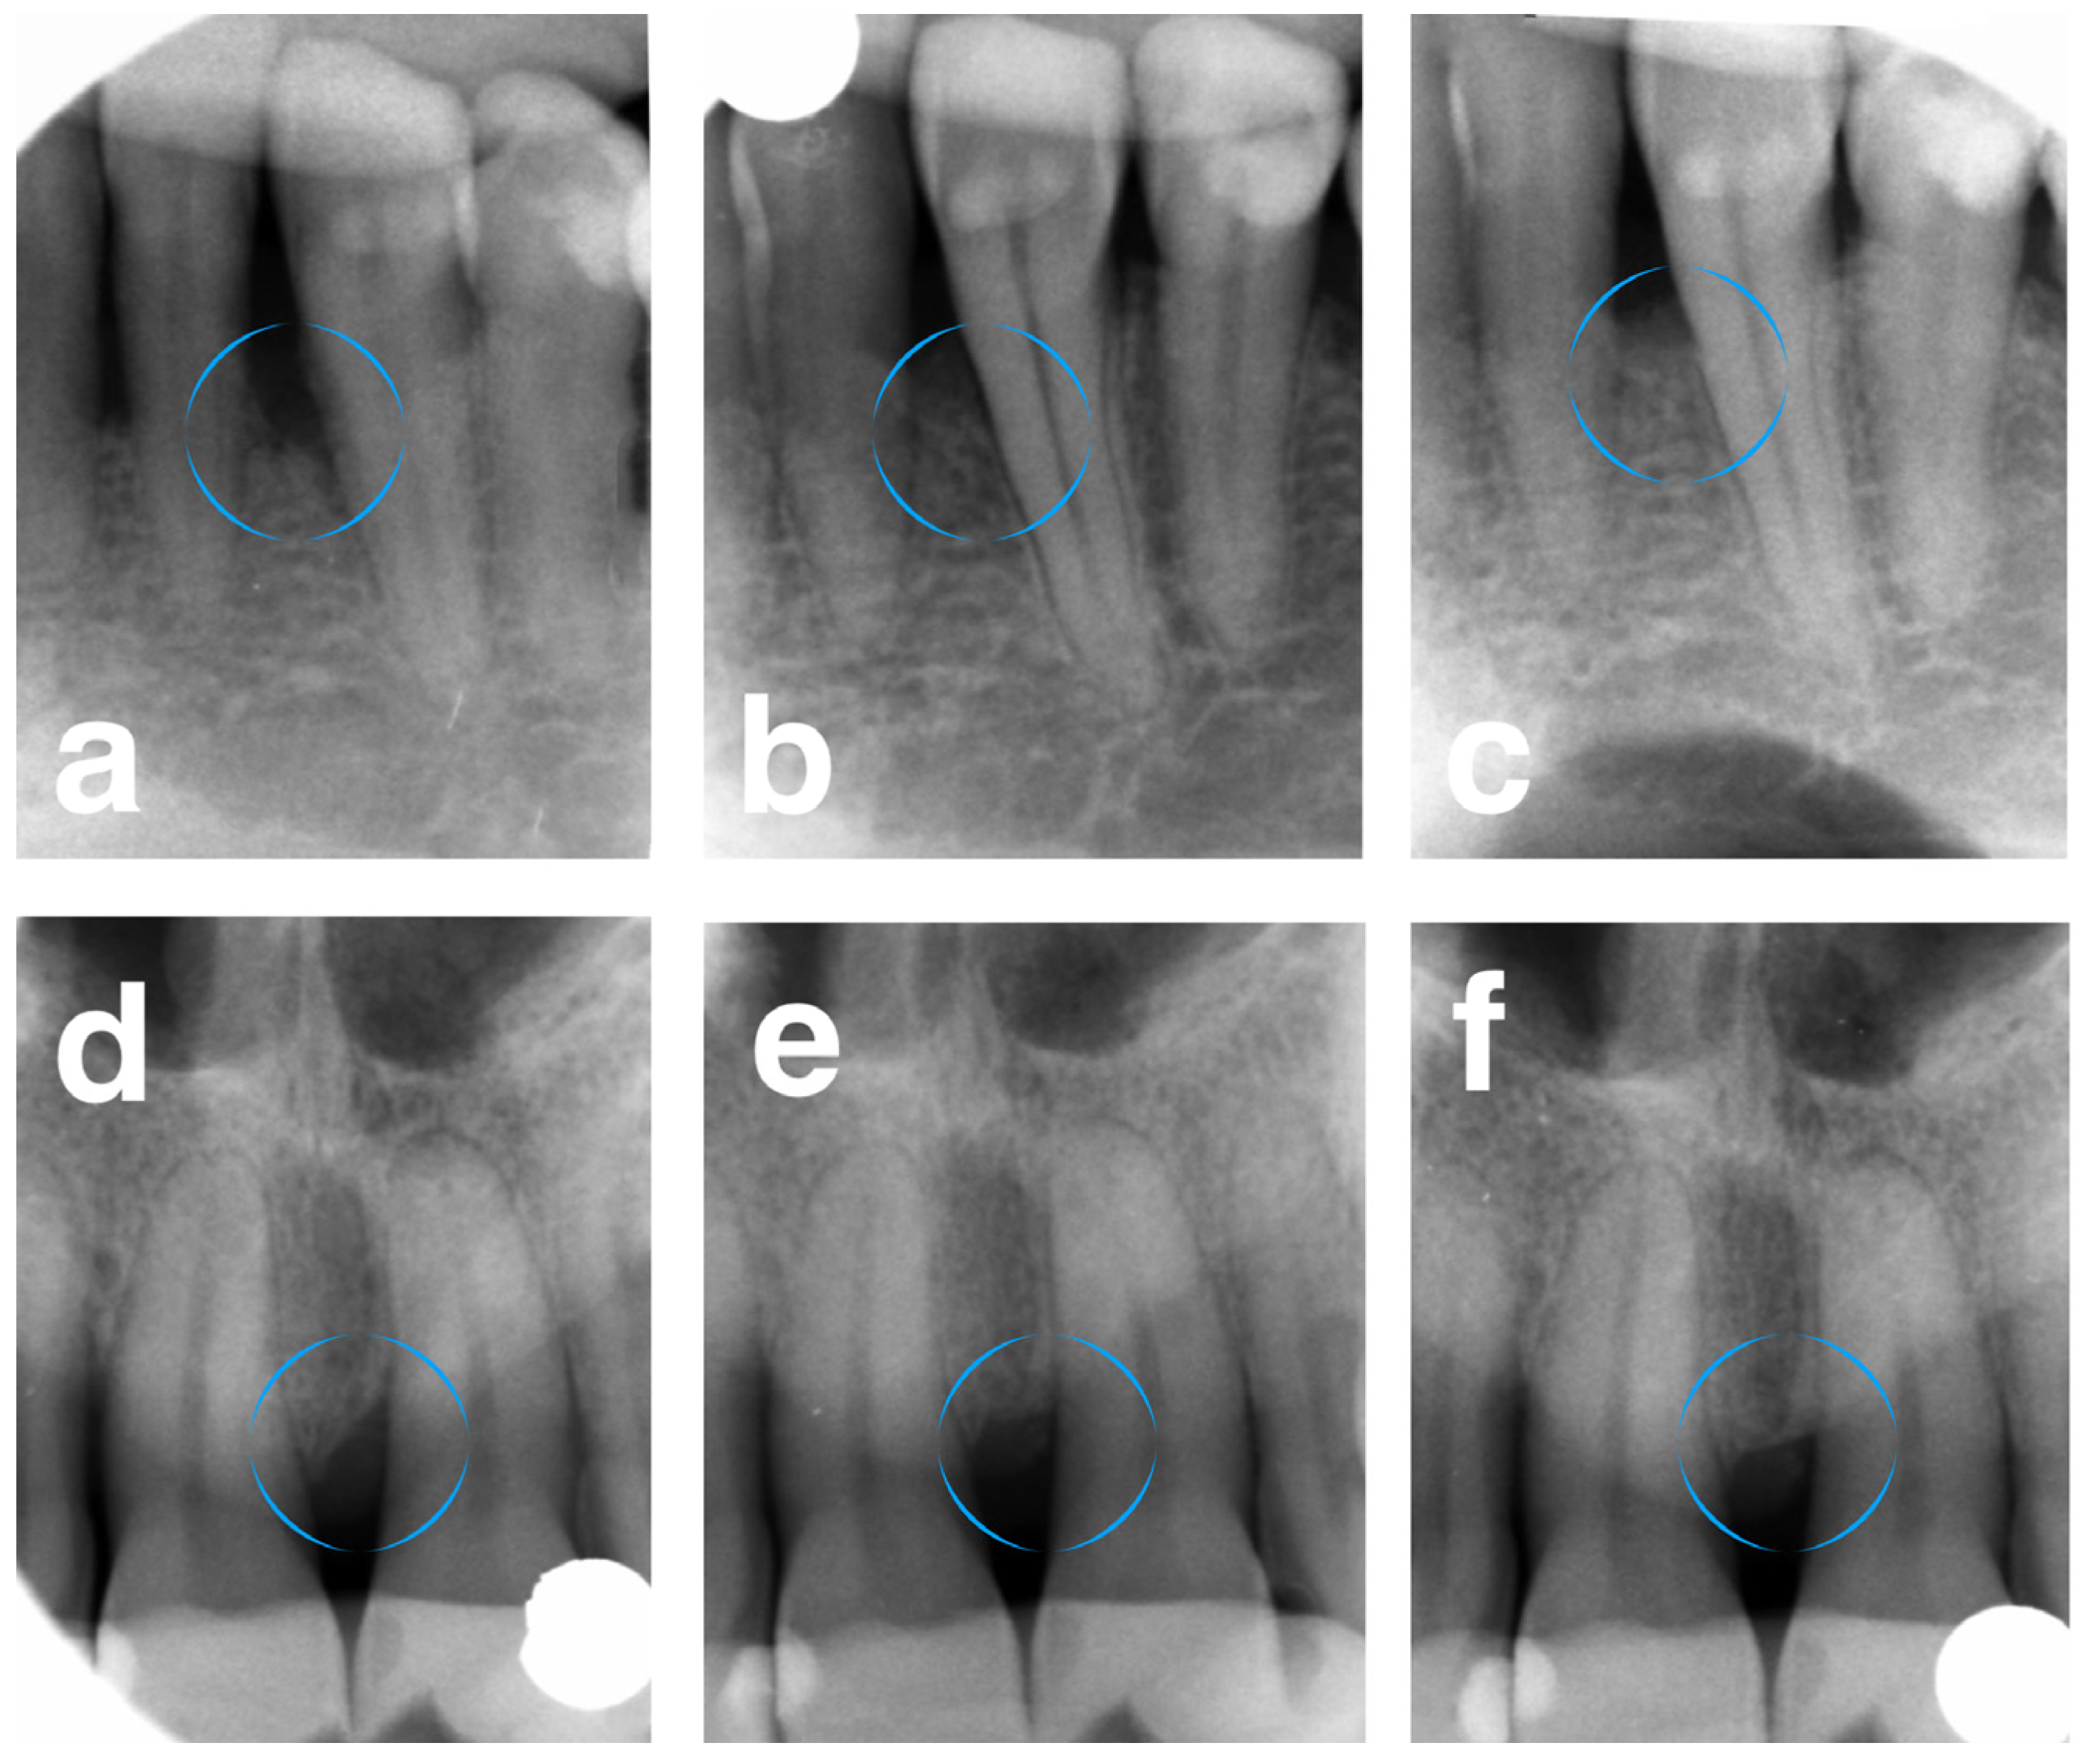

For DD, the FRSBAG group showed significant improvement from 5.89 ± 1.23 to 0.66 ± 0.45 at 1 year and to 0.98 ± 0.62 at 5 years, versus the DBBM group, which demonstrated 5.32 ± 1.84, 0.92 ± 0.61, and 1.14 ± 0.54, pre-operatively, after 1 year, and after 5 years, respectively. The significant intergroup difference was observed at 1 year (p = 0.0334), while insignificant differences were seen at baseline and after 5 years. Similar patterns were demonstrated for LDF and %DF (Figure 2).

Figure 2.

(a) Pre-operative X-ray of the infrabony defect on the mesial surface of tooth 33 (test site). (b) X-ray 1 year post-operatively. (c) X-ray 5 years post-operatively. (d) Pre-operative X-ray of the infrabony defect on the mesial surface of tooth 21 (control site). (e) X-ray 1 year post-operatively. (f) X-ray 5 years post-operatively. Circular outlines highlight infrabony defects.